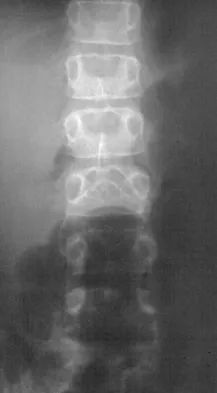

A 44-year-old woman has had lower extremity dysesthesias, urinary incontinence, and has been unable to walk for the past 2 days. She reports no pain or history of trauma. She notes that 3 weeks ago she missed work for 2 days because of back pain, but it resolved with rest. Examination shows decreased or absent sensation below the knees, no motor function below the knees, and decreased rectal tone. Catheterization results in a postvoid residual of 2,000 mL. Plain radiographs and MRI scans without contrast are shown in Figures 1a through 1d. What is the next most appropriate step in management?

Explanation

The patient has had a clear and sudden onset of a profound neurologic deficit. The radiographic studies suggest a lesion in the conus medullaris that appears to be intradural and intramedullary. MRI, with and without contrast, will best evaluate this mass further. The addition of gadolinium allows further evaluation of vascularity and the extent of the lesion. Eichler ME, Dacey RG: Intramedullary spinal cord tumors, in Bridwell KH, Dewald RL (eds): The Textbook of Spine Surgery, ed 2. Philadelphia, PA, Lippincott-Raven, 1997, vol 2, pp 2089-2116.